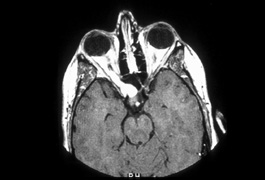

Optic nerve hypoplasia, unless subtle, usually is diagnosed on fundus examination. Although most cases are idiopathic, maternal gestational diabetes and use of phenytoin are well-known risk factors; more recent epidemiologic studies have also suggested that young maternal age, first parity, smoking, and use of fertility and antidepressant drugs may also play a role.27 If bilateral, this condition may be associated with congenital nystagmus. De Morsier's syndrome (septo-optic dysplasia) refers to the constellation of bilateral optic nerve hypoplasia, absence of the septum pellucidum (Fig. 5), thinning or absence of the corpus callosum, dysplasia of the anterior third ventricle, and pituitary dysfunction (see Chapter 5, Fig. 9). Brodsky and Glasier28 broadened the spectrum of this condition. In a study of 40 children, some optic nerve anomalies were isolated, but in other children, midline craniofacial defects, hemispheric gray matter dystrophic anomalies, and posterior pituitary ectopia were noted. Of 21 cases of optic nerve hypoplasia described by Zeki et al,29 there were midline central nervous system defects in six and endocrine deficiencies in nine. In the series of 35 patients with bilateral optic nerve hypoplasia described by Siatkowski et alet al30 neuroradiographic abnormalities were seen in 46% and endocrinopathies in 27%. Growth hormone deficiency was the most common endocrine abnormality. The visual spectrum ranged from 20/20 in one case to no light perception in 34% of patients; 80% were legally blind (20/200 or less in both eyes). Absence of the septum pellucidum and corpus callosum, with panhypopituitarism, occurred in only 11.5% of all patients with bilateral optic nerve hypoplasia. Recently, a sporadic mutation in the HESX1 gene has been reported to cause optic nerve hypoplasia with pituitary insufficiency.31

Fig. 5. Magnetic resonance image of patient with bilateral optic nerve hypoplasia demonstrating absence of septum pellucidum with single midline ventricle.